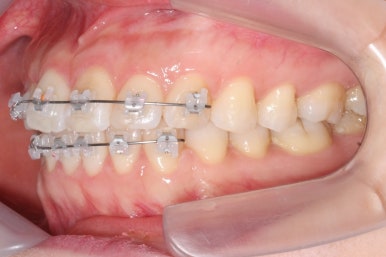

장치를 처음 부착하고 두 번째 조절을 했을 때의 사진입니다.

부분교정의 경우 치료기간을 앞당기기 위해 3주의 내원간격으로 하는 경우가 많은데, 이번의 경우는 결혼식까지 남은 시간이 너무 촉박하여 완벽히 치료를 끝내지 못할 가능성이 컸습니다.

세 번째 조절입니다.

가지런한 정도는 매우 좋아졌고, 군데군데 틈새가 있어서 조여주고 있는 상황입니다.

이정도만 되어도 결혼식을 진행하시기에 어느 정도 만족도 있는 수준까지 왔다고 생각되어졌습니다.